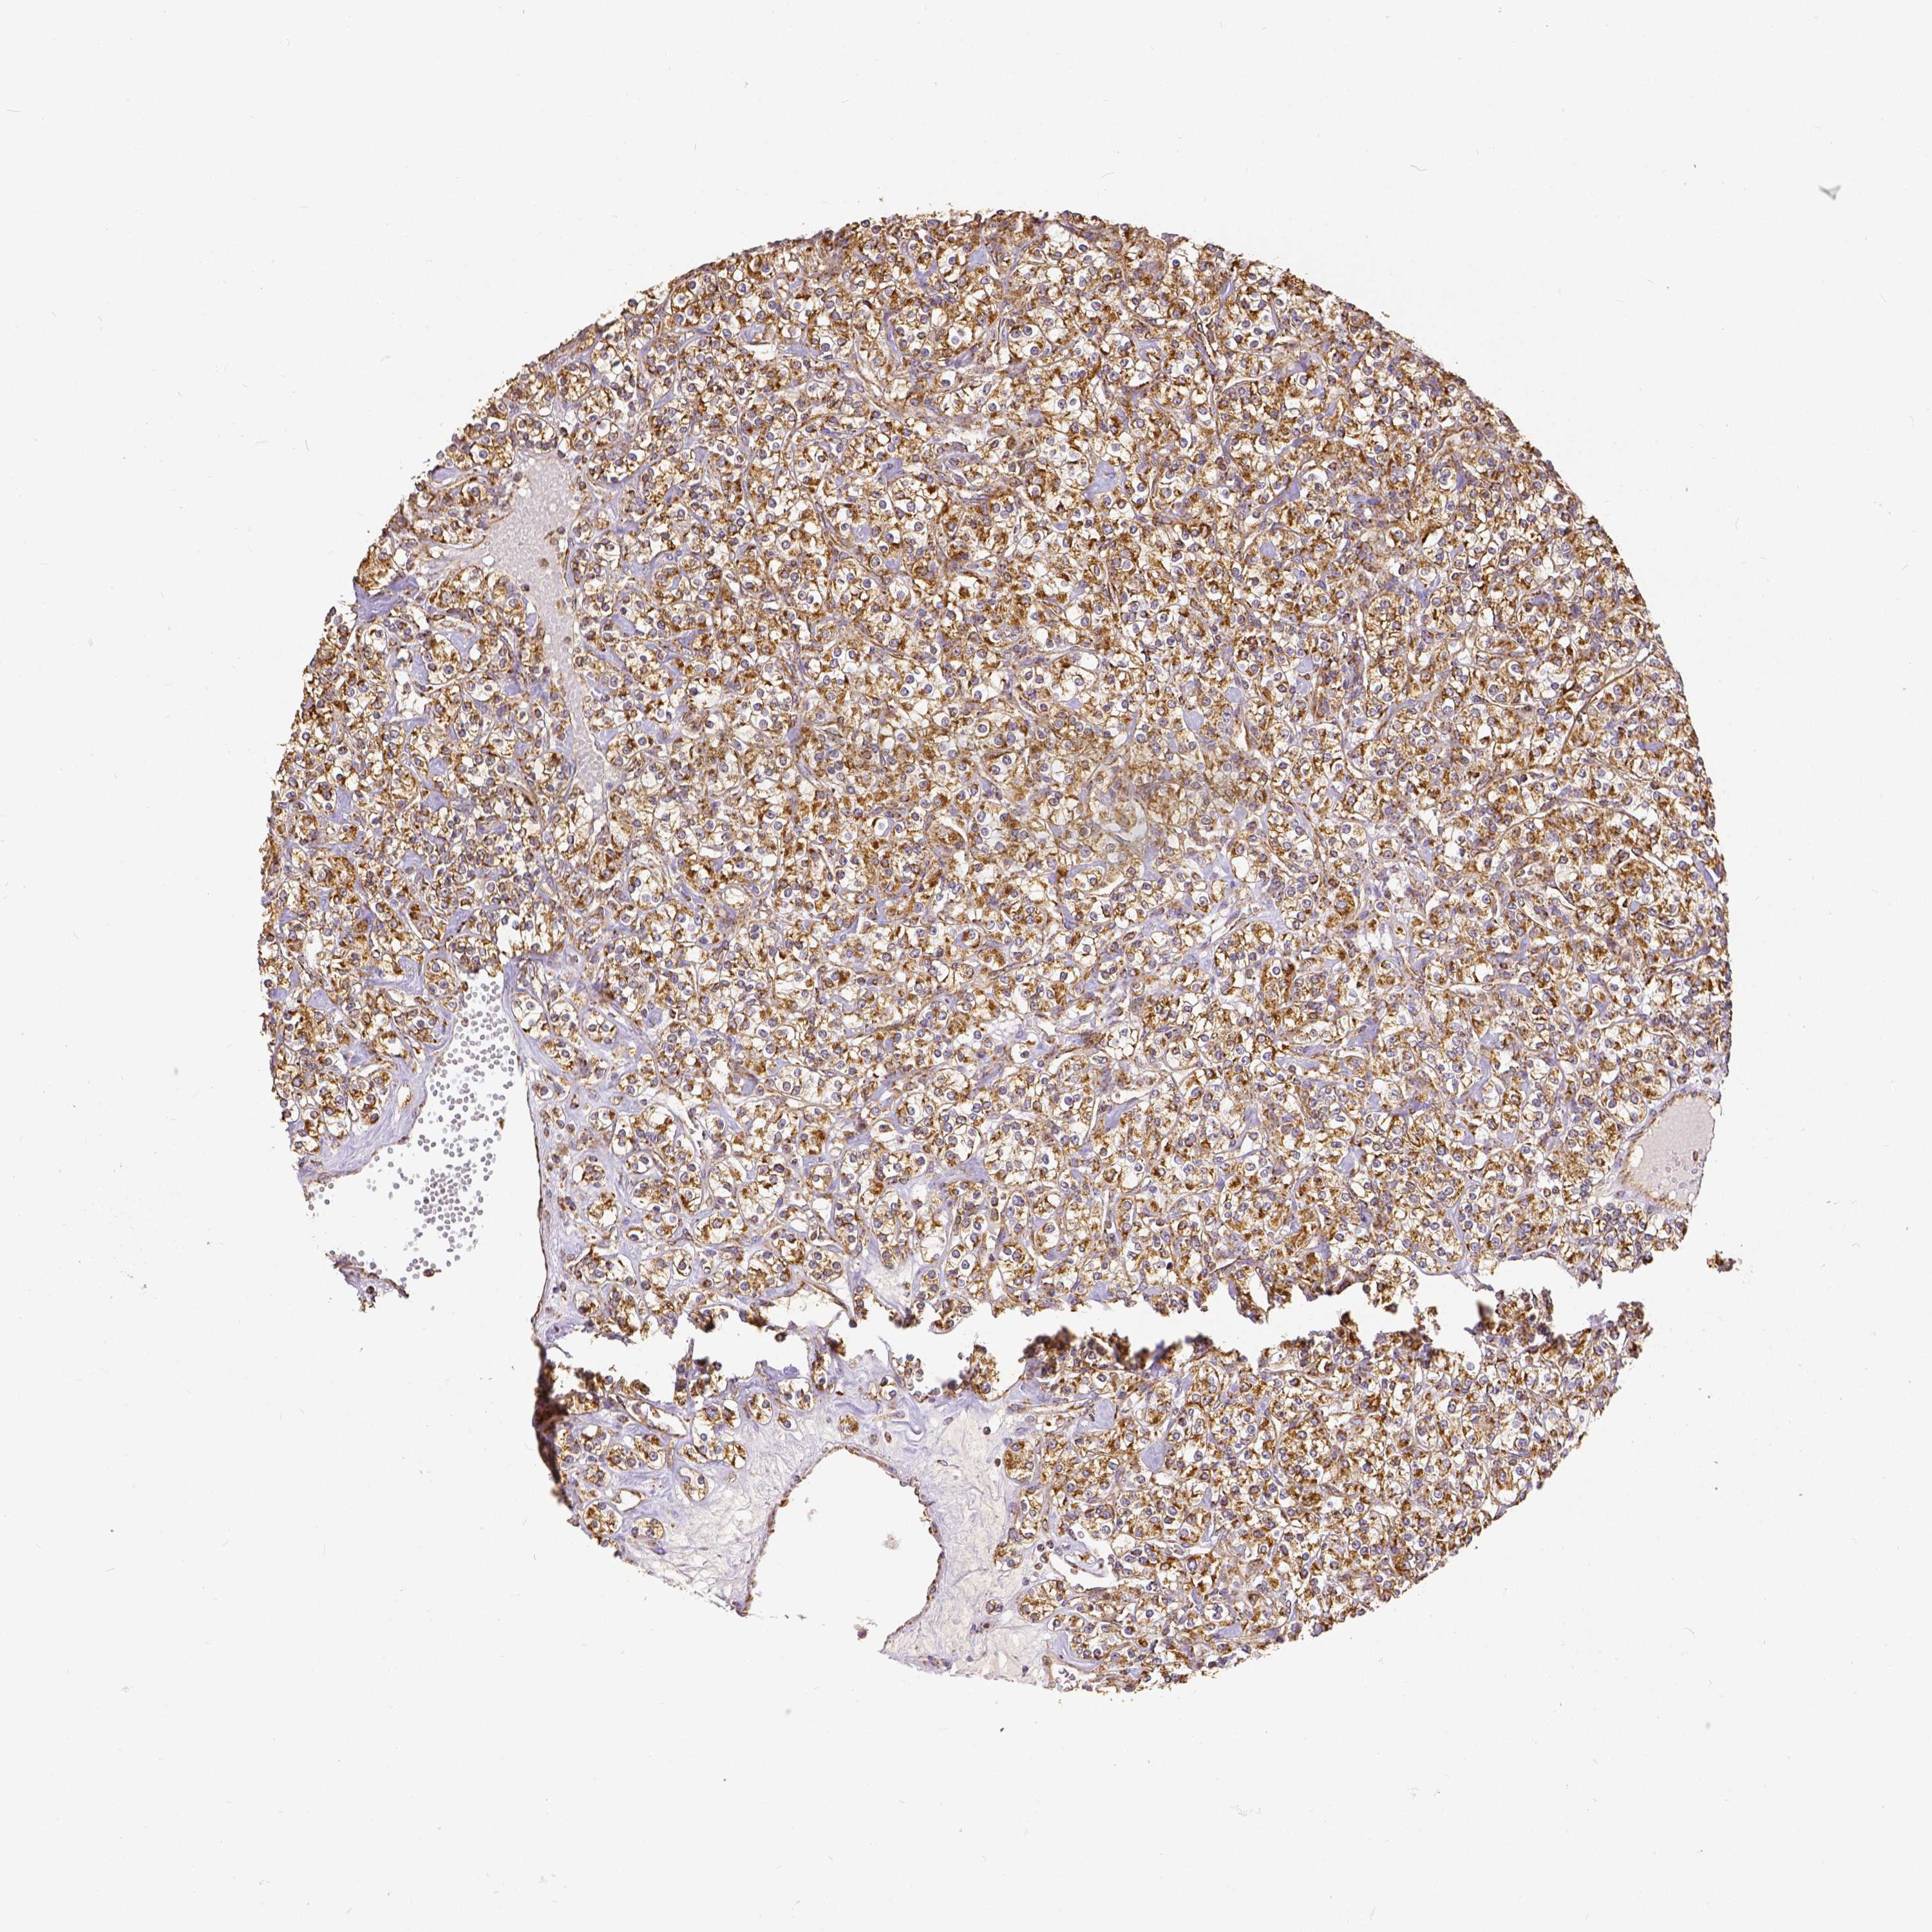

KIDNEY RENAL CLEAR CELL CARCINOMA (TCGA) - Interactive survival scatter ploti

The Survival Scatter plot shows the clinical status (i.e. dead or alive) for all individuals in the patient cohort, based on the same data that underlies the corresponding Kaplan-Meier plots. Patients that are alive at last time for follow-up are shown in blue and patients who have died during the study are shown in red.

The x-axis shows the expression levels (FPKM) of the investigated gene in the tumor tissue at the time of diagnosis. The y-axis shows the follow-up time after diagnosis (years). Both axes are complimented with kernel density curves demonstrating the data density over the axes. The top density plot shows the expression levels (FPKM) distribution among dead (red) and alive patients (blue). The right density plot shows the data density of the survived years of dead patients with high and low expression levels respectively, stratified using the cutoff indicated by the vertical dashed line through the Survival Scatter plot. This cutoff is automatically defined based on the FPKM cutoff that minimizes the p-score. The cutoff can be changed by dragging the vertical line or by entering a cutoff value in the square labeled "Current cut-off".

Under the Survival Scatter plot the p-score landscape (black curve; left axis) is shown together with dead median separation (red curve; right axis). Dead median separation is the difference in median mRNA expression between patients who have died with high and low expression, respectively. It is calculated as follows: median FPKM expression of dead patients with high expression - median FPKM expression of dead patients with low expression. This is intended to aid the user in visually exploring custom cutoffs and the associated p-scores and dead median separation.

Individual patient data is displayed and can be filtered by clicking on one or more of the category buttons on the top of the page. Categories describing expression level and patient information include: high, low, alive, dead, female, male and tumor stages. The scale of the x-axis can be toggled between linear and log-scale by clicking on the "x log" button. Mouse-over function shows TCGA ID, patient information and mRNA expression (FPKM) for each patient.

& Survival analysisi

Kaplan-Meier plots summarize results from analysis of correlation between mRNA expression level and patient survival. Patients were divided based on level of expression into one of the two groups "low" (under cut off) or "high" (over cut off). X-axis shows time for survival (years) and y-axis shows the probability of survival, where 1.0 corresponds to 100 percent.

SDHB is potential prognostic, high expression is favorable in Kidney Renal Clear Cell Carcinoma (TCGA)

Best expression cut offi

Based on the FPKM value of each gene, patients were classified into two groups and association between prognosis (survival) and gene expression (FPKM) was examined. The best expression cut-off refers the FPKM value that yields maximal difference with regard to survival between the two groups at the lowest log-rank P-value. Best expression cut-off was selected based on survival analysis .

When clicking on this number, the vertical dashed line indicating cut-off, the interactive survival plot, and the Kaplan-Meier curve will be adjusted to show results based on the best expression cut-off.

: 87.52

P scorei

Log-rank P value for Kaplan-Meier plot showing results from analysis of correlation between mRNA expression level and patient survival.

N/A

TCGA RNA samplesi

RNA-seq data is reported as average FPKM (number Fragments Per Kilobase of exon per Million reads), generated by the The Cancer Genome Atlas (TCGA) .

Normal distribution across the dataset is visualized with box plots, shown as median and 25th and 75th percentiles. Points are displayed as outliers if they are above or below 1.5 times the interquartile range. FPKM values of the individual samples are presented next to the box plot.

Average pTPM 109.1

Number of samples 521